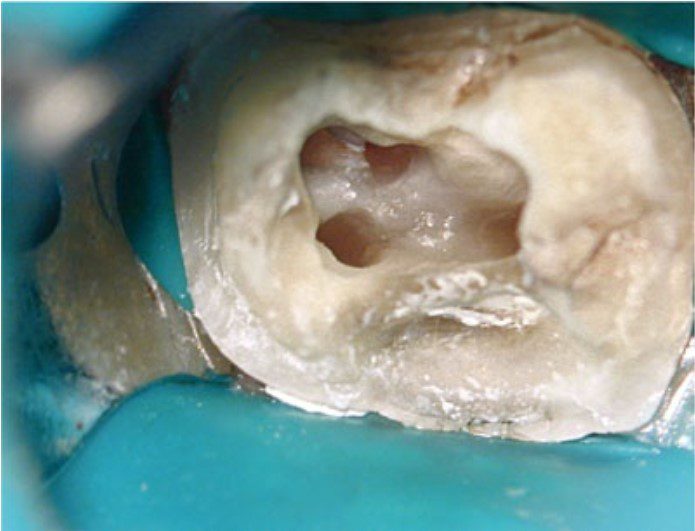

Mở tủy

Nếu xoang mở tủy không đạt yêu cầu thì việc xác định và thăm dò ống tủy sẽ trở nên phức tạp hơn, tiên lượng điều trị sẽ bị ảnh hưởng do bị hạn chế làm sạch, khử khuẩn và trám bít.

Ngoài ra, còn có thể làm tăng nguy cơ gãy dụng cụ và tạo hình sai (ví dụ như lệch đường, tạo khấc), dẫn đến kiểm soát nhiễm khuẩn kém và cuối cùng là thất bại điều trị.

Thực tế thì hiếm khi xoang mở tủy có hình dạng hoàn toàn giống mô tả điển hình trong sách giáo khoa — tức là hình dạng của răng trẻ, chưa từng được phục hồi.

Trên thực tế thì kích thước buồng tủy và vị trí miệng ống tủy bị ảnh hưởng bởi lượng và vị trí ngà thứ cấp, ngà bậc ba được bồi đắp để đáp ứng với sâu răng, phục hồi, rò rỉ hoặc mòn răng theo thời gian.

Những tác động tích lũy này có thể làm thay đổi đáng kể kích thước và hình dạng buồng tủy.

Vật liệu trám bít ống tủy cần kết thúc ở chóp răng tại điểm giới hạn của quá trình tạo hình (điểm thắt chóp). Ở phía thân răng, vật liệu trám bít nên dừng lại cách miệng ống tủy từ 1–2 mm. Trong những trường hợp có tiêu xương nha chu thì phần trám bít nên dừng lại cách mào xương ổ 1–2 mm, nhằm tránh việc vật liệu trám bị lộ ra môi trường miệng qua các ống ngà còn thông.

Nếu có kế hoạch thực hiện phục hình có chốt lưu giữ thì ống chốt nên được sửa soạn ngay sau khi hoàn tất trám bít ống tủy.